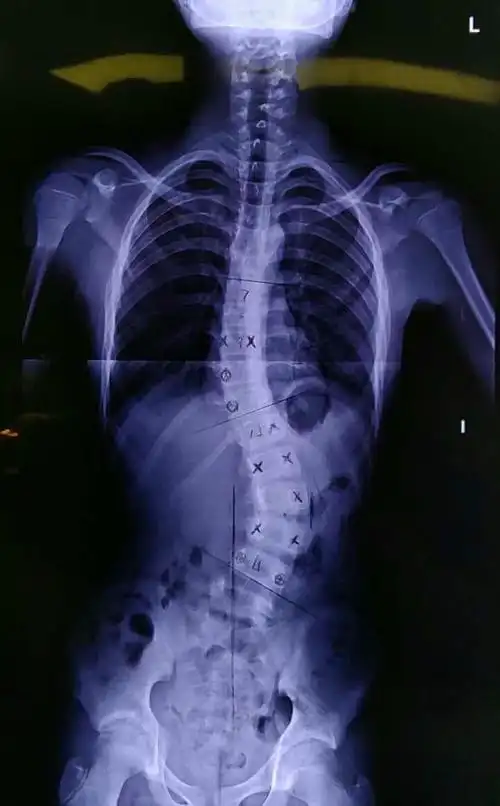

中国孩子脊柱侧弯患病率不容乐观新华医院打造上海脊柱侧弯综合防控与